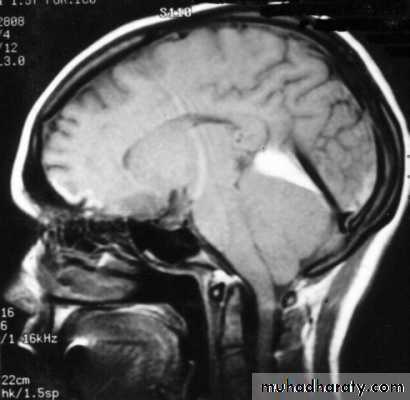

7. Cerebral Herniation

a. Subfalcine Herniation

b. Uncal Herniation

c. Tentorial Herniation

d. Tonsillar Herniation